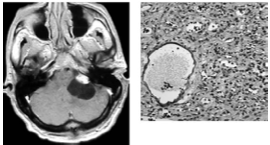

A 54-year-old male who is a heavy smoker presents with balance problems; below are his MRI scan and pathology slide from surgery. This is the most likely diagnosis.

A) Metastasis

B) Hemangioblastoma

C) Glioma

D) CNS lymphoma

E) Pilocytic Astrocytoma

What is B. Hemangioblatoma?

The MRI shows an enhancing mural nodule with an associated cyst. Pathology shows highly vascular tissue and stromal cells characteristic of hemangioblastoma.